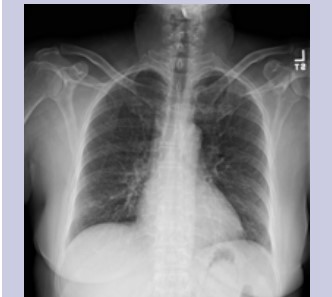

Physical exam was benign. Complete blood count and immunological panel were within normal limits. Spirometry, lung volumes and diffusion capacity were within normal limits. Chest x-ray (Figure 1) showed faint reticular opacities prominent in the mid to lower lobes. Computed Tomography (Figure 2) of the chest showed a diffuse mosaic attenuation pattern. There were multiple pulmonary nodules noted in the right middle lobe. There was no lymphadenopathy. Transthoracic echocardiogram showed impaired left ventricular relaxation with normal LV ejection fraction. Bronchoscopy and transbronchial biopsies of the right upper, middle and lower lobes were performed. Histopathology (Figure 3, Figure 4) revealed mild, nonspecific chronic inflammation. Acid-fast bacilli and fungal stains were negative. There was no evidence of malignancy. Given the persistent symptoms and abnormal CT findings, wedge biopsy of the right upper, middle and lower lobes was performed. Wedge resections showed alveolated lung with expansion of peribronchiolar interstitium by black dust-laden macrophages and dust macules. There were areas of peribronchiolar fibrosis with birefringent silicate and silica material within the interstitium and macrophages. Based on her history of exposure to stone grinding, charcoal and wood burning stoves along with the histopathologic findings consistent with mixed dust pneumoconiosis, she was diagnosed with "Hut Lung” or Domestically Acquired Particulate Lung Disease.

Figure 1: Chest X-Ray showing fine reticular opacities in the mid and lower lungs.